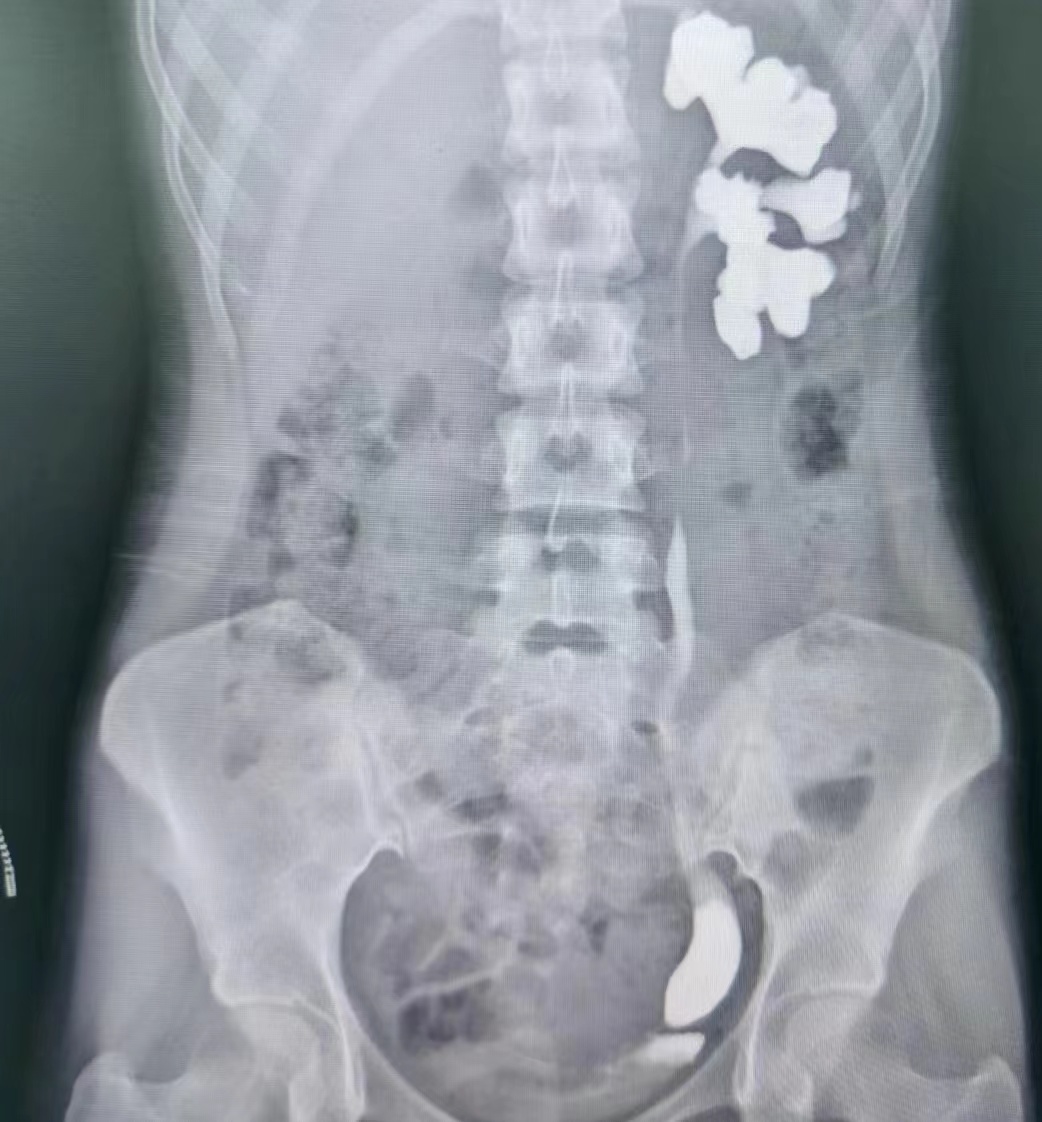

蔡高飞主任医师和王增利副主任医师诊疗组将患者收住入院,入院后行静脉肾盂造影和逆行肾虚输尿管造影提示左侧输尿管末端狭窄。科主任赵卫红立即组织全科讨论,由于输尿管下段走行毗邻髂血管和子宫动脉和卵巢、输卵管,术中稍有不慎损伤髂血管则会引起大出血,损伤子宫附件则会影响生育功能。考虑到患者年龄较小,本着手术效果和术后美观的原则,根据本科室近年来在腹腔镜手术方面的积累,决定为其实施腹腔镜下输尿管再植术,此手术方式创伤小,出血少,术中视野好,术后恢复快。